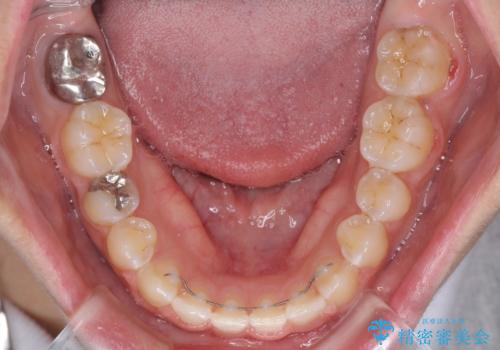

すきっ歯は後戻りを起こしやすいため、上下ともに歯の裏側を細いワイヤーで固定した上で、リテーナーのマウスピースを装着していただいています。